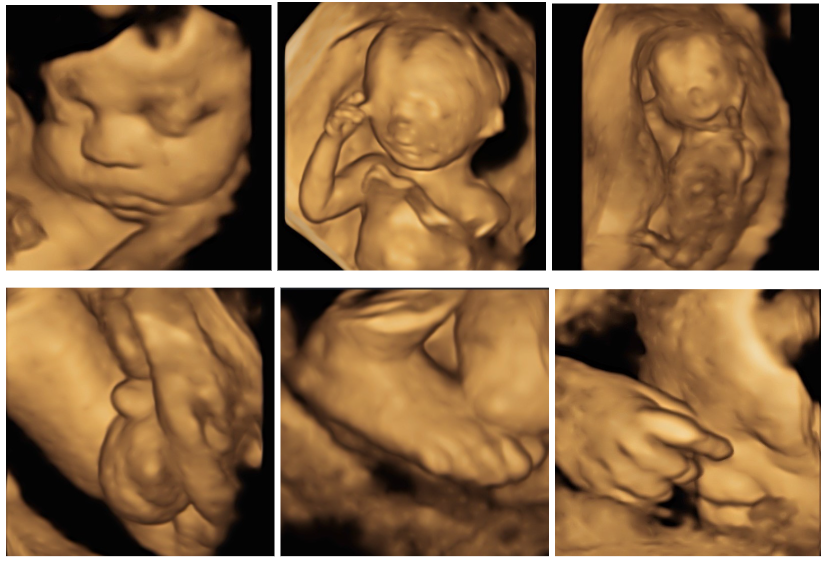

อัลตราซาวด์ 4 มิติ

– ใช้ในการดูรูปใบหน้า และลักษณะภายนอกของทารกได้ดี

– อาศัยการประมวลผลจากหัวตรวจชนิดพิเศษ

– ภาพมีลักษณะเป็น 3 มิติเสมือนจริง เป็นภาพนิ่ง สีเนื้อ

– มิติที่ 4 จะเป็นการถ่าย VDO แบบ Real-time ขณะตรวจค่ะ